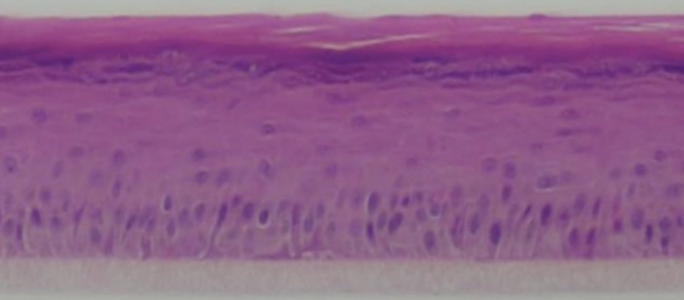

BioDEpi

Human Skin Epidermis

The BioDEpi models are constructed using normal epidermal keratinocytes sourced from human tissues after obtaining the necessary ethical consent from the patients. These cells are isolated and cultured using inhouse developed serum free media to obtain the maximum undifferentiated cellular population. These cells are cultured on transwell inserts with a pore size 0.4μm to culture these tissues at an air-liquid interface as native tissue, resulting in the formation of a multilayered and highly differentiated model that faithfully mimics the structure and characteristics of the native human epidermis. The resemblance of the BioDEpi model to the native human epidermis highlights its authenticity and suitability for various applications in research, including dermatological studies and drug development.